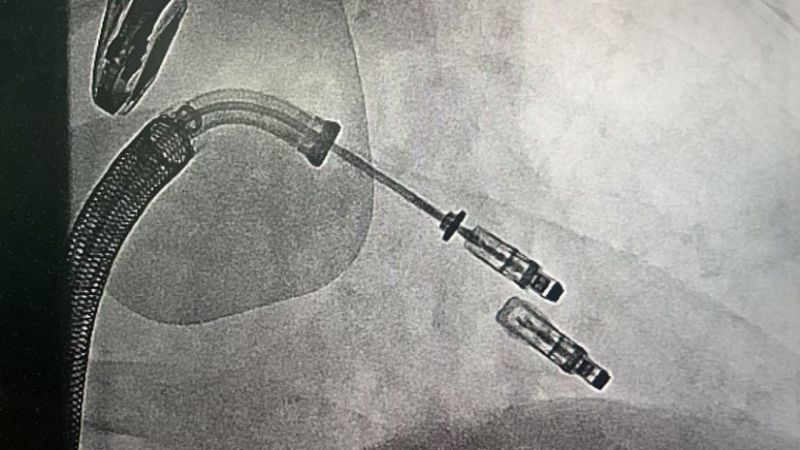

手术于11月4日下午进行,通过股静脉穿刺送入夹合器,在食道超声实时引导下,精准植入2枚瓣膜夹修复二尖瓣。整个过程历时约2小时,术中出血量仅50ml。术后次日,患者即可下床活动,复查显示EF提升至46%,二尖瓣返流面积缩小至3.0cm²,左心房缩小至66mm,胸闷、气短症状明显缓解。

1.微创路径:经股静脉穿刺,无需开胸或体外循环;

2.精准定位:在食道超声和X线引导下,将夹合器送达二尖瓣位置,通过夹合病变瓣膜减少返流;